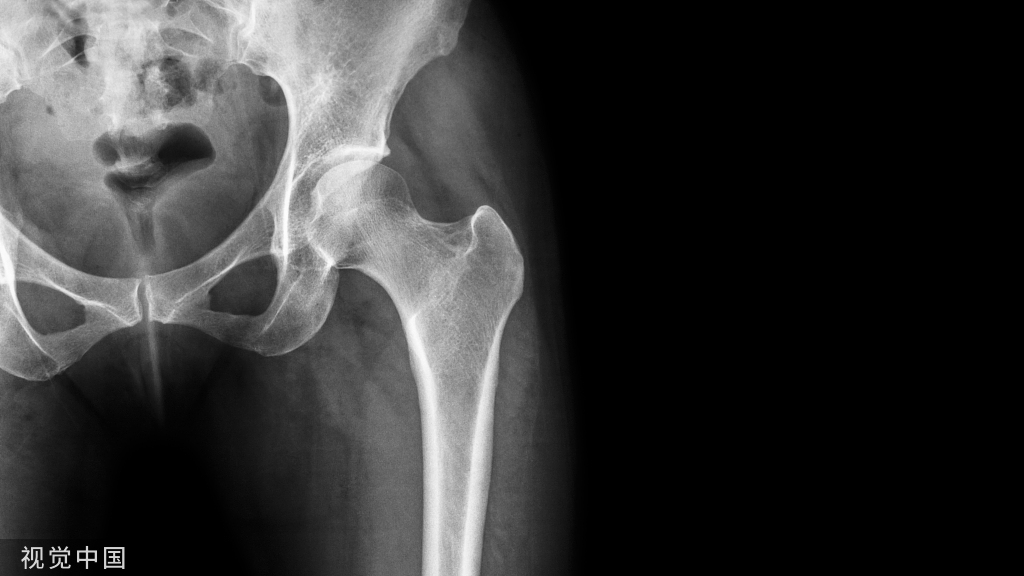

三、半月板小骨

半月板小骨的病因尚不确定,但可能是创伤后或残留的结构,可能无症状或与局部疼痛有关。它们最常见于内侧半月板后角内;在平片上经常被误认为是游离体。在MRI能够显示半月板小骨位于半月板内,并容易误诊为半月板磨损并撕裂。